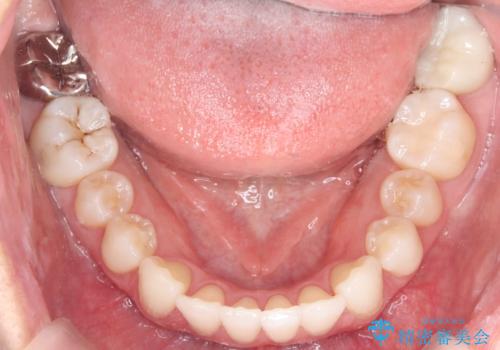

- 前歯のデコボコ(叢生)と、前歯が上下逆の咬み合わせ(反対咬合)を主訴にご来院されました。精密検査の結果、歯列全体のスペースが不足していることが判明。患者様のご希望に合わせ、透明で目立ちにくい**インビザライン(マウスピース矯正)**による治療計画を立案しました。歯を抜かずに、歯列全体を奥(遠心)へ移動させることで、歯が並ぶスペースを確保し、叢生と反対咬合を同時に改善することを目指します。

今回の矯正治療では、透明なマウスピース型の装置インビザラインを使用しました。この装置は目立たず、取り外しが可能なため、食事や歯磨きも普段通り行えます。治療は、緻密な治療計画に基づき、段階的に作製されたマウスピースを交換していくことで、遠心移動という方法で奥歯から徐々に歯列全体を後方へ動かしました。これにより、不足していたスペースを確保し、前歯のデコボコを解消。同時に、上下の歯の前後的な関係を改善することで、反対咬合も正常な咬み合わせへと導きました。見た目も機能も改善し、自然で美しい笑顔を獲得していただけました。